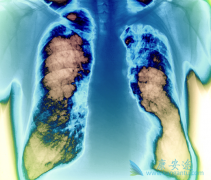

肝癌是我们国内第二代的癌症恶性肿瘤,这与我国大量的肝炎患者的存在密不可分。在过去我们肝癌治疗手段比较有限,绝大多数丙肝患者都是采用的是化疗的方式来治疗丙肝。但其实丙肝的治疗并不仅仅只有化疗。化疗存在巨大的毒副作用,所以很多丙肝患开始采 ...

间皮瘤 作为一种隐匿性肿瘤,可发于胸膜腔、腹膜腔、睾丸鞘膜或心包的间皮表面,其中大部分病例源于胸膜。恶性胸膜间皮瘤(MPM)是最常见的恶性间皮瘤,绝大多数MPM患者发病年龄在60岁及以上,石棉暴露是发生胸膜间皮瘤最重要的危险因素。大部分患者因逐 ...